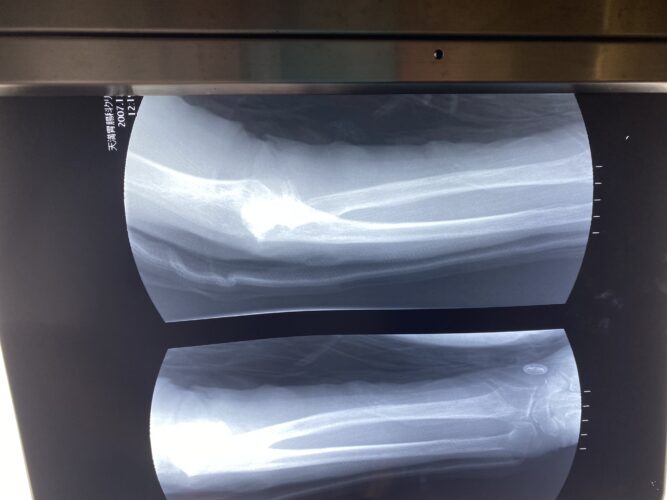

第25回整骨研究会「賜恩」研修会開催

春日部市市民活動センター(前腕骨骨幹部骨折)

第26回整骨研究会「賜恩」研修会開催